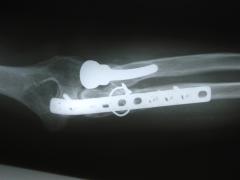

Περίπτωση 1ου ασθενούς

4 χρόνια μετά το χειρουργείο